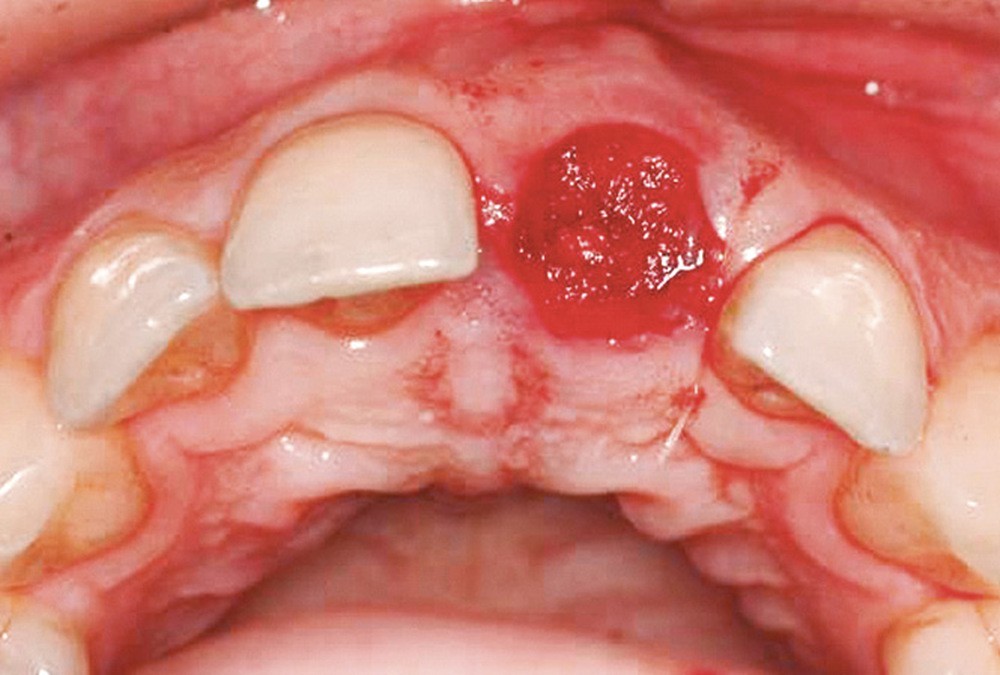

Mais c’est surtout la conséquence à moyen terme de l’avulsion dentaire qui retiendra ici notre attention, car elle signe essentiellement le déclenchement d’un processus de remodelage cicatriciel au niveau de l’alvéole, qui aboutit à une perte plus ou moins importante du volume de la crête résiduelle. Cette altération morphologique, si elle n’est pas contrôlée et maîtrisée, aura des conséquences certaines sur les aspects esthétiques et prophylactiques de toutes nos reconstructions prothétiques fixées, dento- ou implantoportées.